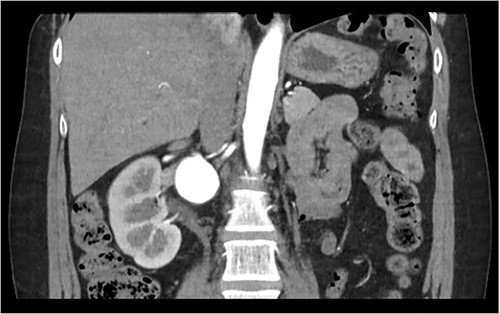

Computed Tomography (CT) renal angiogram was consistent with prior imaging, demonstrating a 3.8 cm right renal aneurysm, multicystic dysplastic appearance to the left kidney with no functional left renal tissue (Fig. 1). Hence, vascular surgery consultation was advised.